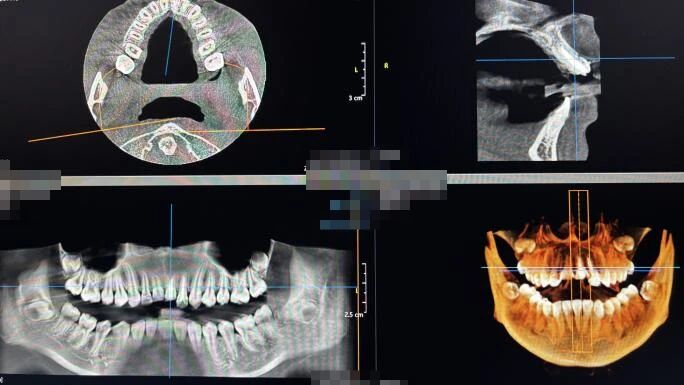

根管治疗的CBCT影像